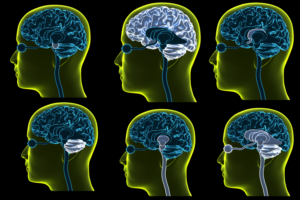

transparent 3D concussion booklet